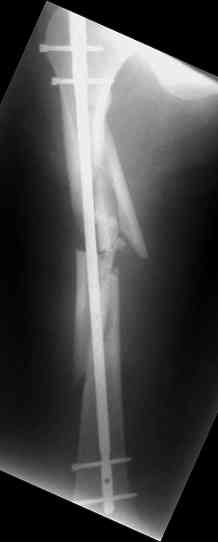

одна проблема в моей компьютерной неграмотности(не смог прикрепить снимки), а другая в том, что связь с пациентом потеряна и,насколько я понял в своем регионе ему посоветоваться не с кем, кроме главного врача который отреагировал на выбранную нами тактику так: "там тебя использовали в качестве подопытного кролика...".

Надеюсь сейчас показать перелом, а потом синтез.